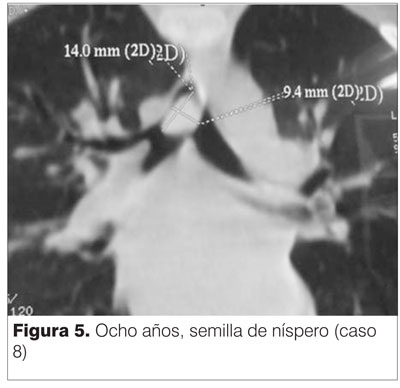

En el caso 8 se realizó TAC que localizó el CE en la carina (figura 5).

El niño del caso 8, de ocho años, provenía de Tacuarembó al cual ante sospecha de aspiración de CE pese a radiología normal se le practica TAC que localiza el mismo en carina (figura 5, semilla de níspero), siendo enviado para su extracción al HP.

Aunque se afirma que ni la tomografía computada, ni imágenes digitales ni la resonancia magnética ofrecen ventajas sobre los métodos radiológicos descritos, en el paciente del caso 8 la TAC puso en evidencia el CE ante la sospecha de aspiración, a pesar de una radiografía normal. También fue normal la radiografía practicada (a una hora del episodio asfíctico) al niño de cuatro años (caso 7) que mientras juega aspira la tapa de un bolígrafo en su casa.